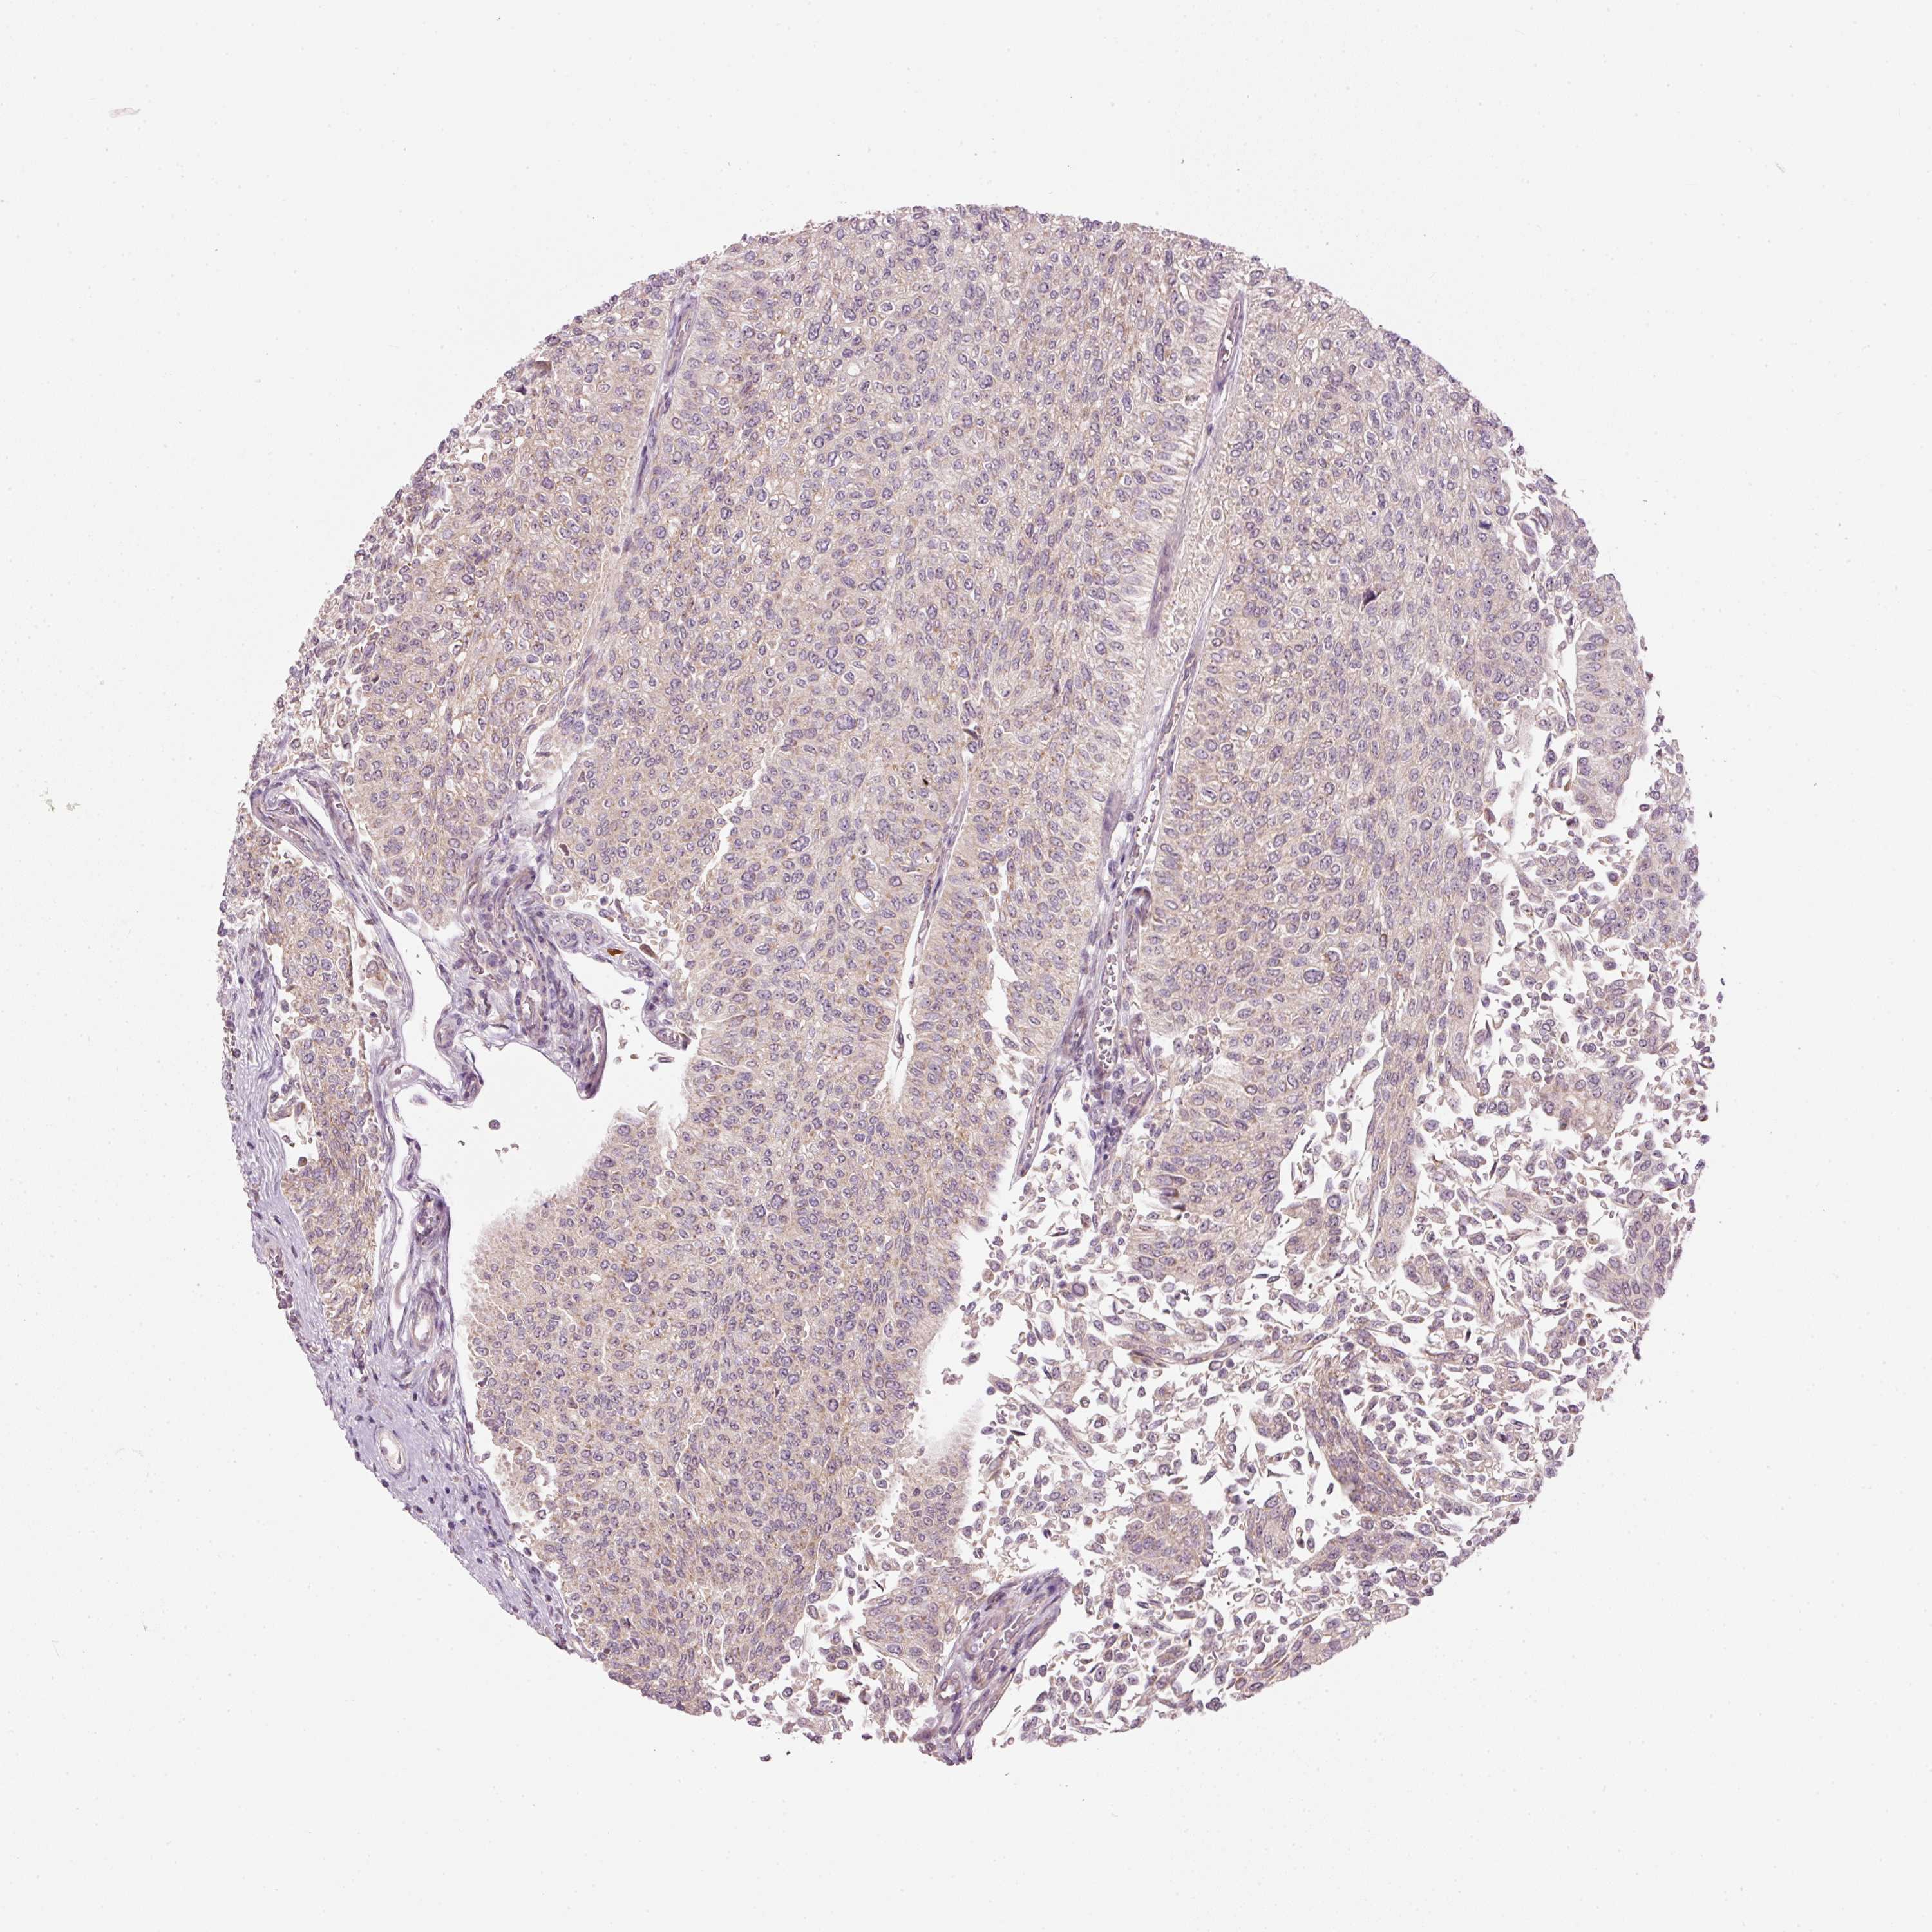

UROTHELIAL CANCER - Protein expressioni

A mouse-over function shows sample information and annotation data. Click on an image to view it in a full screen mode. Samples can be filtered based on level of antibody staining by selecting one or several of the following categories: high, medium, low and not detected. The assay and annotation is described here.

Note that samples used for immunohistochemistry by the Human Protein Atlas do not correspond to samples in the TCGA dataset.

Antibody stainingi

Antibody staining in the annotated cell types in the current human tissue is reported as not detected, low, medium, or high, based on conventional immunohistochemistry profiling in selected tissues. This score is based on the combination of the staining intensity and fraction of stained cells.

Each image is clickable and will lead to virtual microscopy that enables deeper exploration of all samples and also displays staining intensity scores, fraction scores and subcellular localization as well as patient and tissue information for each sample.

Antibody HPA053900

Staining

High

Medium

Low

Not detected

Intensity

Strong

Moderate

Weak

Negative

Quantity

>75%

75%-25%

<25%

None

Location

Nuclear

Cytoplasmic/membranous

Cytoplasmic/membranous,nuclear

Urothelial carcinoma, High grade

Urothelial carcinoma, NOS

Urothelial carcinoma, Low grade